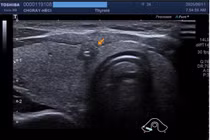

Hiện nay, FNA chủ yếu được thực hiện dưới hướng dẫn của siêu âm, giúp bác sĩ quan sát rõ vị trí cần chọc và đảm bảo kim được đưa chính xác vào nhân giáp hoặc hạch nghi ngờ. Điều này không chỉ nâng cao độ chính xác chẩn đoán mà còn giúp thủ thuật an toàn hơn, tránh tổn thương mạch máu hoặc cấu trúc lân cận.